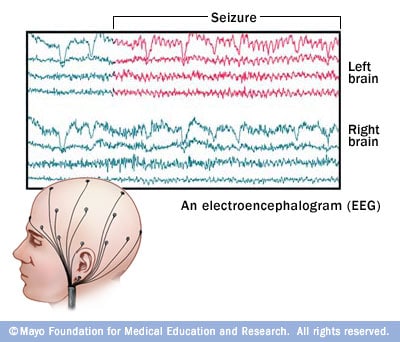

Surgery is most commonly done when tests show that your seizures originate in a small, well-defined area of your brain that doesn't interfere with vital functions such as speech, language, motor function, vision or hearing. In surgery, your doctor removes the area of your brain that's causing the seizures.

If your seizures originate in an area of the brain that controls movement, speech and other functions, you may be awake during part of the surgery. Doctors will monitor you and ask you questions during the procedure.

If your seizures originate in a part of your brain that can't be removed, your doctor may recommend a different type of surgery in which surgeons make several cuts in your brain (multiple subpial transection). These cuts are designed to prevent seizures from spreading to other parts of your brain.